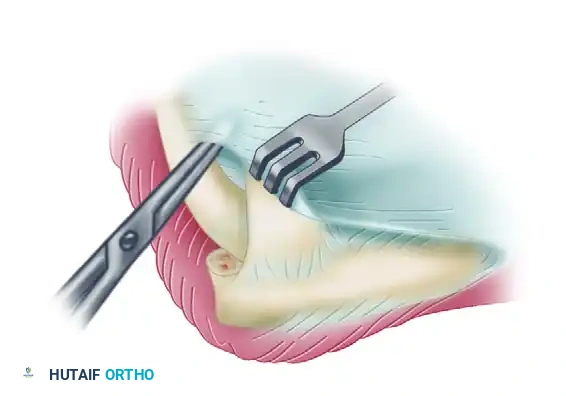

Posterior Dissection and Capsulectomy

Once the anterior release is complete, attention is turned to the posterior compartment to restore elbow flexion.

- To preserve periosteal continuity and optimize triceps function postoperatively, elevate the triceps tendon subperiosteally from the posterior aspect of the humerus and the tip of the olecranon.

- Retract the mobilized triceps posteriorly and medially to expose the underlying posterior joint capsule and the olecranon fossa.

- Perform a posterior capsulectomy, again proceeding from lateral to medial.

- Ulnar Nerve Precaution: Take extreme care not to venture too far medially during the posterior capsulectomy. The ulnar nerve lies immediately posterior to the medial epicondyle in the cubital tunnel. If extensive medial capsular release or medial osteophyte excision is required, a separate medial incision to decompress and protect the ulnar nerve is strongly advised.